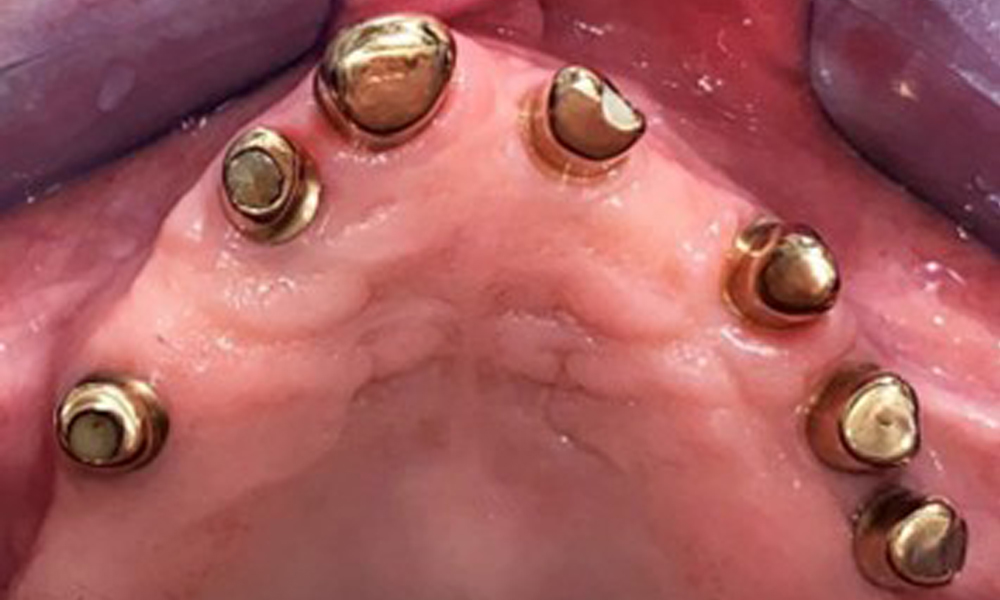

Okklusalansicht: Oberkiefer mit Zahn- und implantatgetragenen Teleskopen.

Abb. 2: Okklusalansicht: Oberkiefer mit Zahn- und implantatgetragenen Teleskopen.

Der dentale Befund stellt sich wie folgt dar: Kombinierte herausnehmbare Implantat- und zahngetragene Teleskoparbeit auf Implantaten 15, 13, 21, 23, 24, 25 und Zahn 11 (Abb. 1, Abb. 2, Abb. 3). Im Unterkiefer ist die Patientin mit einem festsitzenden Zahnersatz versorgt. 37–34 sowie 45–47 haben suffiziente Brücken (Abb. 4). Kronenränder sind intakt, aktive kariöse Läsionen sind nicht vorhanden. An Zahn 43 zeigt sich eine Compositefüllung mit Randspalt. Im Unterkiefer liegen Rezessionen mit freiliegender Wurzeloberfläche zwischen 1 – 3 mm vor. Dies trifft auch für 11 zu.

Die Patientin wurde vor über 25 Jahren mit einer kombinierten herausnehmbare Implantat-Teleskopprothese im Oberkiefer versorgt (Abb. 1, Abb. 2, Abb. 3) und ist sehr glücklich über ihren Zahnersatz. Im Unterkiefer hat die Patientin einen suffizienten festsitzenden Zahnersatz. (Abb. 4)